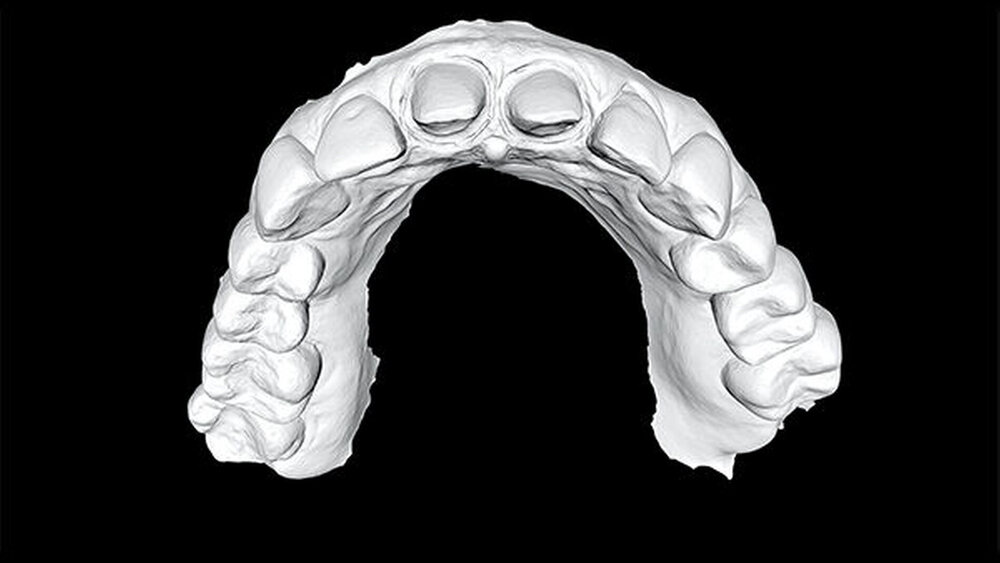

… diese Erfahrung machen wir nicht. Wir scannen grundsätzlich den gesamten Ober- und Unterkiefer. Wir hatten eine entsprechende Einführung von 3Shape, zudem gibt es hervorragende Onlinetutorials dazu. Wir haben inzwischen ein eigenes Konzept entwickelt. Während die Anästhesie wirkt, legen wir mit Optra Gate und Dry Tips trocken und machen einen Vorscan. Die zu beschleifenden Zähne werden aus dem Scan ausgeschnitten. Dann wird präpariert und die Präpgrenzen werden dargestellt. Zum Schluss werden nur noch die präparierten Zähne und die Bisslage gescannt.

Man kann auch konventionell nur das abformen, was man sieht, das ist also nichts Neues. Eine deutliche und gute Darstellung der Präparationsgrenzen war schon immer ein Muss. Die Präparationsgrenzen habe ich in der Vergangenheit – wie gesagt – stets akribisch am Modell unter dem Mikroskop dargestellt. Der Scanner hat nun den entscheidenden Vorteil, dass man Zahn für Zahn abscannen kann und jeweils nur eine Präpara‧tionsgrenze darstellen muss (Abb. 15). Das klappt erheblich einfacher und schneller, gerade wenn man mehrere Pfeiler hat. Noch leichter funktioniert das beim Implantatscan.

Zusätzlich kann das Emergenzprofil bereits intraoperativ in der Implantationssitzung gesteuert werden. Der Scan der ausgeheilten Situation vor der prothetischen Versorgung eröffnet die Möglichkeit, durch Einmatchen des Implantats in den Datensatz die subgingivale Situation zu simulieren ohne die Darstellung einer „Präparationsgrenze“ durch das Einlegen von Fäden. Diese Manipulationen sind traumatisch und zerstören die sensible hemidesmosomale Anhaftung der Gingiva- und Bindegewebsfasern an der Implantatoberfläche. Der digitale Abdruck wird die konventionelle Abformung in der modernen Zahnarztpraxis aufgrund seiner überlegenen Performance ersetzen. Den parodontologischen und minimalinvasiven Prinzipien folgend, ist die digitale Abformung von Zähnen auch in der ästhetisch sensiblen Zone angesichts der geringeren Traumatisierung der parodontalen Gewebe, der überragenden Präzision und der daraus folgenden Randpassung der Versorgung ein logischer und richtiger Weg in die Zukunft der zahnärztlichen Praxis (Abb. 10 – 14).

Faszinierend und lange vermisst ist für den funktionsanalytisch und -therapeutisch tätigen Zahnarzt die Möglichkeit der Relationsbestimmung ohne Materialien auf der Okklusion. Die therapeutische Bisslagebestimmung zur Anfertigung von Aufbissbehelfen beispielsweise mit anteriorem Jig und seitlichem „Bisslagescan“ ermöglicht die Anfertigung spannungsfreier Schienen mit definierter therapeutischer Gestaltung der okklusalen Kontakte und Führungsflächen.